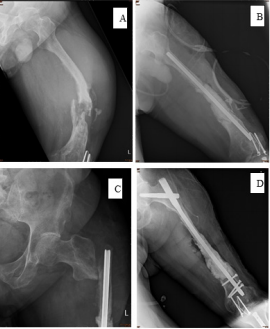

The patient visited our OPD again and was thus referred to the Orthopedic oncology surgeon for evaluation. Clinical exam showed a 6 x 4 cm, firm, irregular, immobile mass extending from the anterior to the lateral aspect of left thigh. There was no numbness or weakness or sensory defect in the affected lower limb. Radiography revealed ill-defined osteolytic lesions with sclerotic changes in left distal femur. MRI showed enlargement of granulation tissue and hematoma with adjacent bone destruction. We repeated the surgery of tumor excision. The final pathology result was identical with previous finding (squamous epithelial hyperplasia with mild atypia). After discharge for four months, sudden onset of left thigh pain was noted at distal part after standing up at home. At emergency department, radiography revealed left distal femur osteolytic lesion with impending pathological fracture (Figure 3A). Angiography was arranged for further evaluation, which revealed a bulky hypervascular soft tissue with malignancy characteristic in the left upper thigh. During the operation, massive yellow-brownish pus with lymphangio-like lobulated mass were found.

In order to correct distal femur varas deformity, we performed valgus osteotomy and fixation with Kuntsher nail (10mmx300mm), and Vancomycin-coated cement spacer at fracture site (Figure 3B). The final histopathology revealed squamous cell carcinoma. However, he complained left hip pain after bedside ambulation one week later. Radiography showed left hip subtrochanteric pathological fracture, so we exchange the Kuntsher nail with Cephalomedullary nail for fixation (Figure 3C & 3D). On the outpatient department follow-up, poor skin healing with fistula purulent discharge was still noted. Repeated MRI revealed tumor progression with involvement of gluteal muscle, anterior compartment of thigh, and left inguinal area, and the whole-body bone scan (Figure 4) had increased uptake over left inguinal area. Several debridement and tumor wide excision provided little help, so he underwent above-knee amputation. Five months later, left anterior palpable mass with anterior thigh pain and skin tenting was noted again. Repeat MRI (Figure 5) revealed recurrence of malignant tumor, lymphadenopathy in the left groin region, and peri-acetabular bone metastasis. Thus, we preceded with left hemipelvectomy (Figure 6) and skin coverage with local fasciocutaneous flap. After the surgery, the patient received adjuvant chemotherapy therapy. The pain resolved, and there was no marked local recurrence over a period of 2 years.

Figure 3: Anteroposterior

A. X-ray revealed distal femur pathological fracture with varus deformity,

B. Kuntsher nail for internal fixation with vaconcomysin-coated cement,

C. Left femur subtrochanteric pathological fracture (one week after Kuntsher nail fixation),

D. Remove Kuntsher nail and use long cephalomedullary nail.